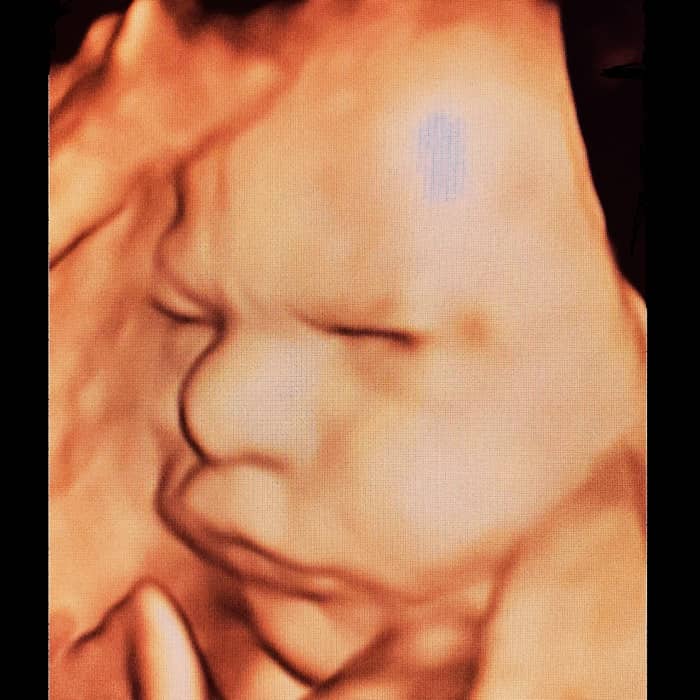

Kliniğimizde yapılan ayrıntılı ultrason muayenelerinden 4 boyutlu ultrason örnekleri:

3 boyutlu renkli ultrasonda derinliği de yansıtan üç boyutlu bir görüntü vardır. Bebek renkli olarak görüntülenir. 2 boyutlu ultrasona göre daha net ve belirgin bir görüntü vardır.

4 boyutlu ultrason (4D ultrason) görüntü özellikleri açısından 3 boyutlu ultrasona benzer. 4 boyutlu ultrasonun farkı hareketli olmasıdır. Bir anlamda anne karnındaki bebeğin video görüntüsüdür.